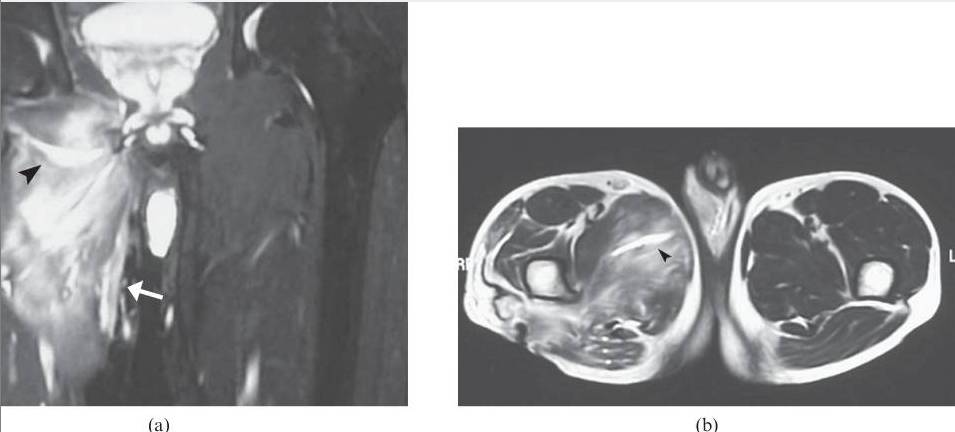

![]()

图8.26岁女性多发性肌炎,呈现双侧下肢疼痛和肌肉无力。(a)大腿的轴向T2加权的MR图像显示在股外侧肌,中间肌,内侧肌和股直肌(箭头)的异常,广泛的羽状水肿。注意保持正常的肌肉结构。T1加权成像(未显示)在受影响的肌肉中未显示信号改变或萎缩,或在此情况下有助于诊断。(b)两腿的冠状动脉脂肪抑制的T2加权的MR图像还在小腿的肌肉(箭头)中显示广泛的水肿信号。右腓肠肌的内侧头显得幸免(箭头)。